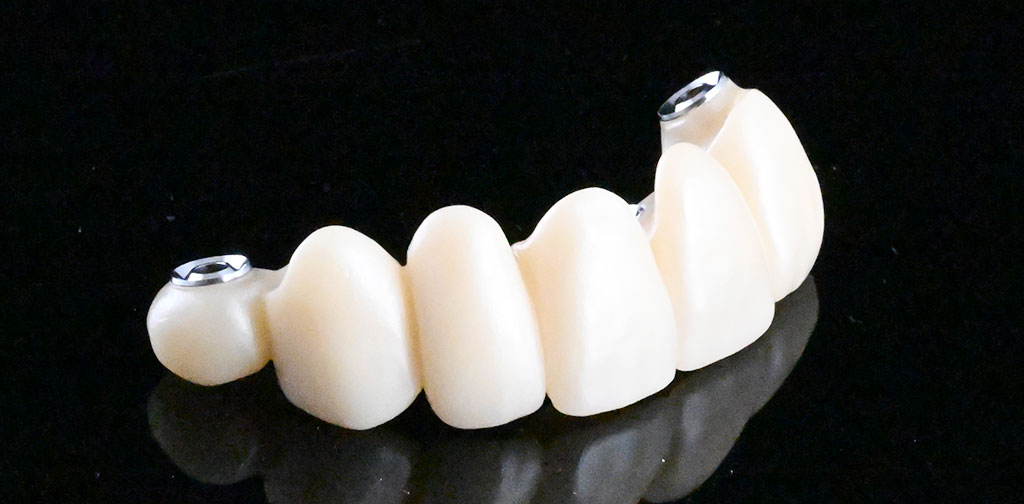

セットした上部構造

左上1,2番、右上4番インプラント治療

(右上4番、左上1,2番)インプラント埋め込み・上部構造:275,000円/1本×3=825,000円